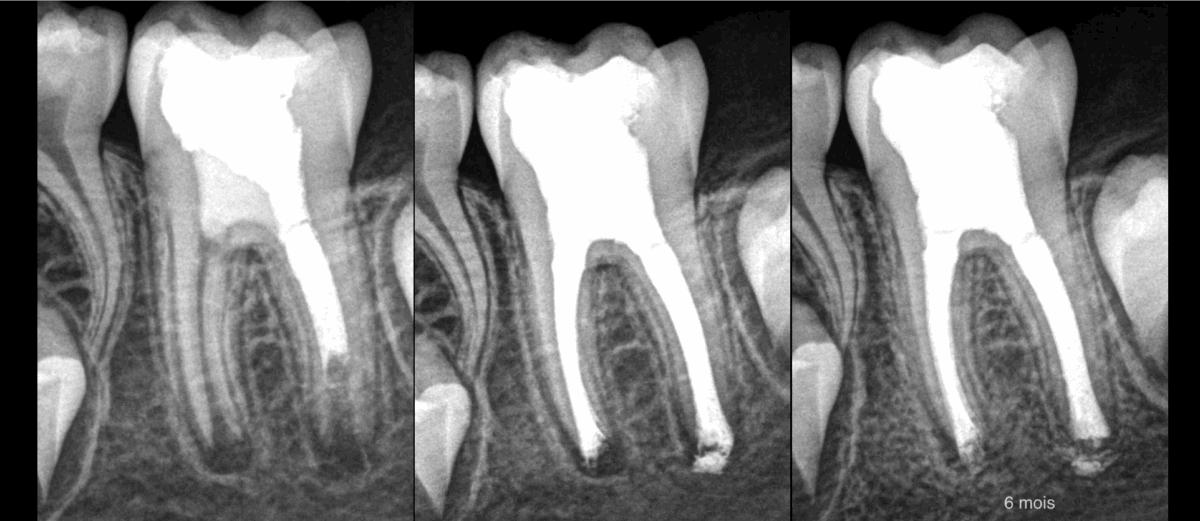

🦷 𝐃𝐏𝐈 : 𝐜𝐨𝐦𝐦𝐞𝐧𝐭 𝐠𝐞́𝐫𝐞𝐫 𝐝𝐞𝐬 𝐜𝐚𝐧𝐚𝐮𝐱 𝐚𝐮𝐬𝐬𝐢 𝐥𝐚𝐫𝐠𝐞𝐬 𝐬𝐮𝐫 𝐜𝐞𝐭𝐭𝐞 𝐦𝐨𝐥𝐚𝐢𝐫𝐞 ?

Dans ce cas : obturation monocône à froid avec ciment biocéramique.

📍 𝐀𝐟𝐢𝐧 𝐝𝐞 𝐠𝐮𝐢𝐝𝐞𝐫 𝐚𝐮 𝐦𝐢𝐞𝐮𝐱 𝐥𝐚 𝐛𝐢𝐨𝐜𝐞́𝐫𝐚𝐦𝐢𝐪𝐮𝐞 𝐚̀ 𝐥’𝐚𝐩𝐞𝐱, 𝐥𝐞𝐬 𝐜𝐨̂𝐧𝐞𝐬 𝐝𝐞 𝐠𝐮𝐭𝐭𝐚 𝐨𝐧𝐭 𝐞́𝐭𝐞́ 𝐦𝐨𝐮𝐥𝐞́𝐬.